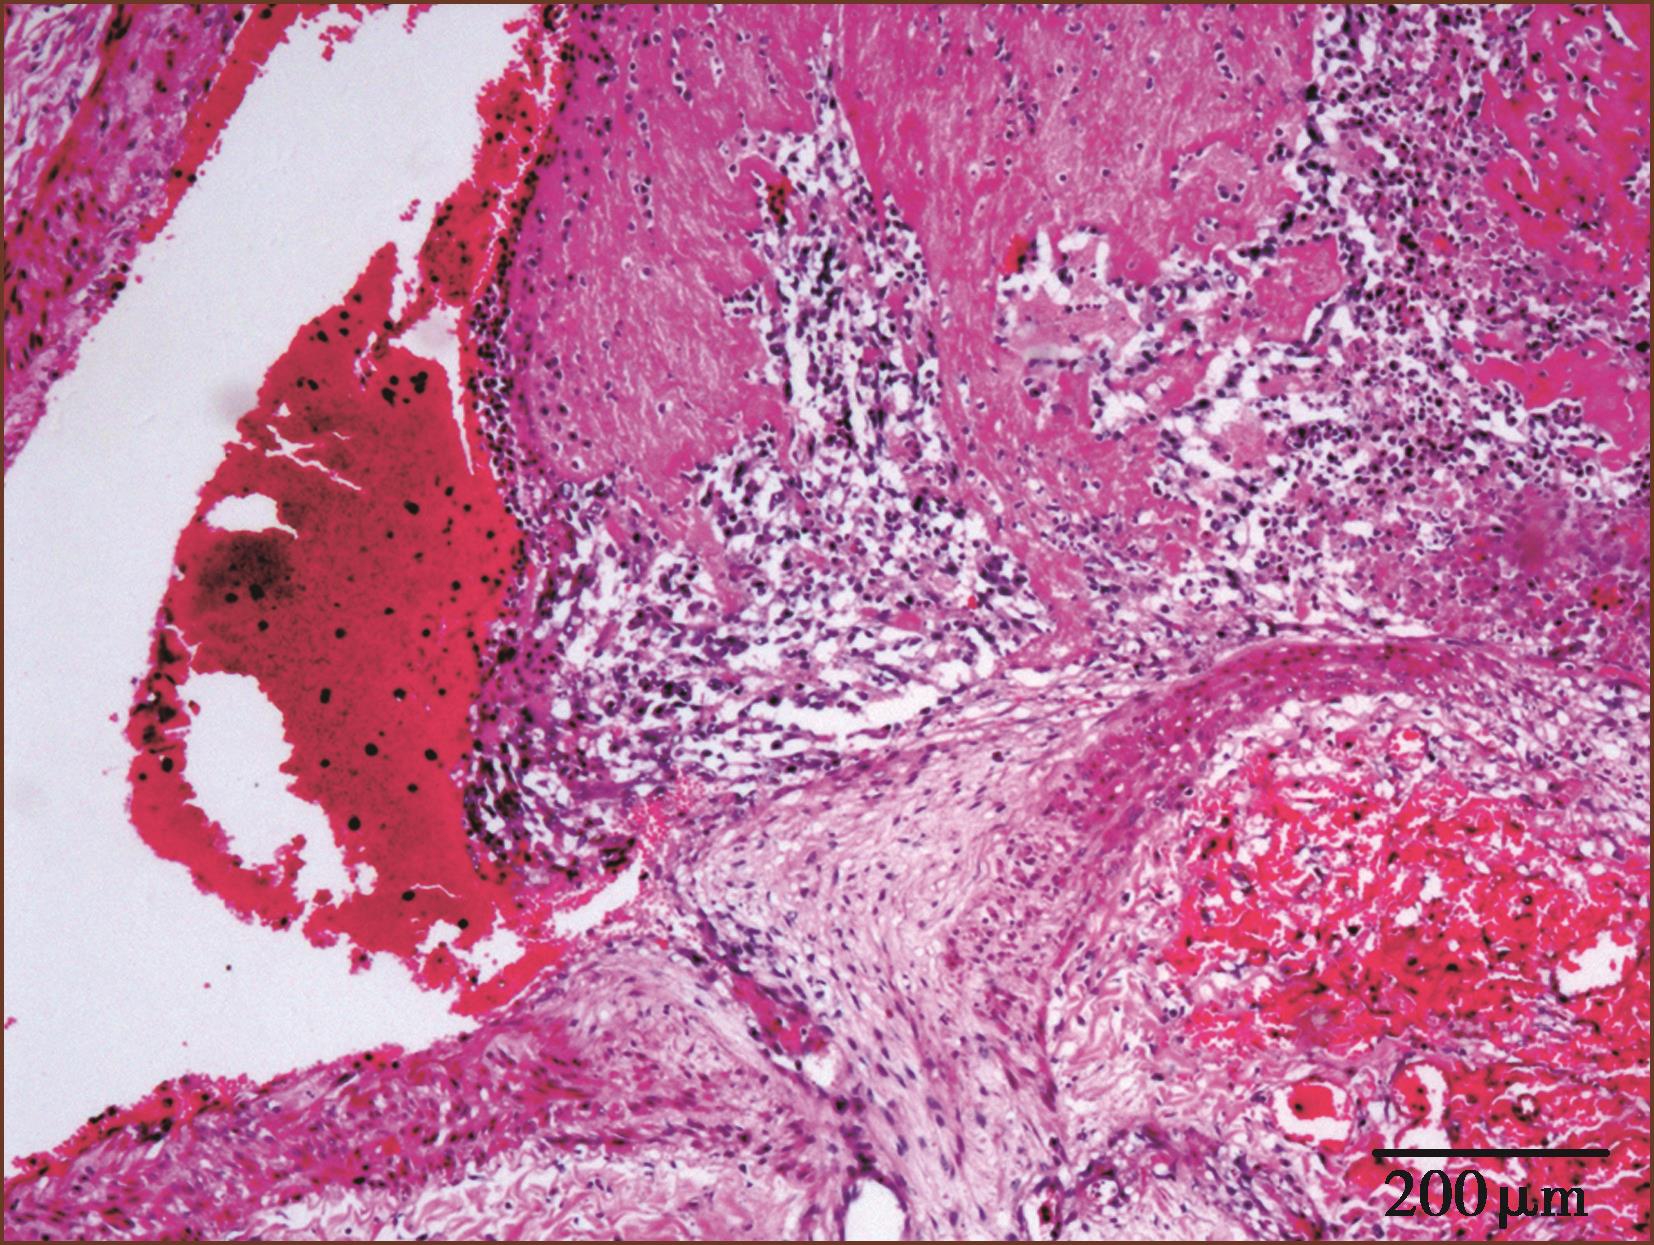

慢性栓塞时,肺动脉内膜增厚,多为机化血栓(图3-2-3)。血栓可以再通,在原有机化血栓基础上又可见新鲜血栓形成(图3-2-4,图3-1-8)。

图3-2-3 肺动脉血栓机化(HE染色,低倍放大)

没有可靠的标准区别是原位血栓形成,还是栓塞,一般认为,大肺动脉的血栓阻塞可能来自栓塞,常为急性;肺动脉末梢分支血栓阻塞可能是原位的血栓形成。肌型肺动脉血栓很可能是原发的,虽然肺小动脉广泛的微栓也可从大块血栓崩解而来。慢性血栓性肺动脉病常常伴发肺动脉高压,血栓的病理变化特征是不规则的、非板层状闭塞性内膜纤维化,有机化再通的血管,有时为血管内纤维性单一分隔或网状分隔。可伴有肺毛细血管芽增生,像丛状。血栓后病变的可逆性是很有限的。有的病人临床有不能解释的肺动脉高压,其肺肌型动脉有多个新旧血栓阻塞;但其体静脉无栓塞病史,此种被称为安静型反复发生的血栓栓塞性肺动脉高压(silent recurrent thromboembolism pulmonary hypertension),又可称为慢性血栓栓塞性肺动脉高压(CTEPH)。此种微栓可能由于原发的血栓形成,而不是栓塞。我们也遇到过此种原因不明的特发性肺动脉高压,临床误诊为先天性心脏病或间质性肺病。在血栓后的肺小动脉纤维斑块内可见含铁血黄素沉着或钙化。在有些血栓阻塞型肺动脉高压病例,肺小动脉中层肥厚不如动脉性肺动脉高压那样的明显,而以内膜纤维化及血栓改变明显。

(二)血栓的病理进展性变化

据国外的有关实验报道,机体对血栓有自溶作用,少量小块血栓栓子2~3周会自溶消失。血栓如不溶解,血管及其滋养血管扩张,约12小时后会有纤维素覆盖表面,约24小时后有内皮细胞开始覆盖,局部动脉中膜水肿,中性粒细胞浸润入血栓附着的内膜面,动脉内弹力板开始被破坏。2~3天血栓与内膜粘连,内皮细胞植入血栓内。一周后血栓明显机化反应,纤维肌母细胞、纤维母细胞、内皮细胞、新生毛细血管增生,中性粒细胞浸润渐减少,淋巴细胞渐增多,有含铁血黄素的吞噬细胞、单核细胞、浆细胞浸润。2~3周后血栓机化反应使其能牢固地与局部动脉壁粘连,血栓有纤维肉芽组织、新生小血管,使血栓机化再通。机化血栓有的呈偏心性纤维化,或完全纤维化闭塞,或管腔内膜纤维化增厚,被一纤维条状分隔成双腔,或筛孔状再通。受累动脉内膜弹力板可崩解、分裂变细、减少。